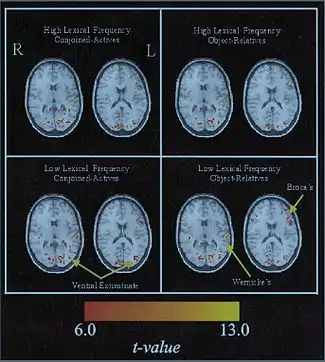

However, a recent study explores the notion of an inter-related network being drawn upon for lexical processing. An fMRI was conducted on subjects to examine lexical and syntactic processing in reading comprehension using a lexical decision task. Results from the study suggest that a variety of lexical and syntactic factors affected activation of a wide portion of the left hemisphere, including the aforementioned perisylvian areas, as opposed to being localized in a specific area.[8] A similar purported view is that the interaction of different areas of the brain enhances the efficacy of lexical access.[9][10] From the study of the activation of brain cortical regions using fMRI, it was deemed that several areas were integral for lexical processing, and not just confined to one modality as previously thought. A point of consensus is that the left inferior frontal gyrus is indeed involved, however, its role is in question. Some researchers assert that the left IFG (also containing Broca’s area) is concerned with semantic processing of words, while others stipulate that is involved in the selection of multiple meanings.[11]

In terms of interpreting visual data, the ventral extrastriate cortex has been found to play a role in early processing of visual word form, giving rise to subsequent phonological or semantic processing. [21] Studies on orthographic forms of lexical access have specified a number of regions activated by visual lexical decision tasks, including the occipital pole, lateral and basal occipito-temporal lobes, the superior and middle temporal gyri and the inferior parietal lobule.[22]

In particular, the lateral extrastriate cortex was attributed to actively processing the visual information; the left medial extrastriate cortex was found to be most activated by the actual word, and word-like stimuli. It is interesting to note that activation in these regions was seen bilaterally as well; this challenges the notion that language stems solely from the left hemisphere. It can be surmised the right hemisphere plays a role in visual word-form lexical access.[23]